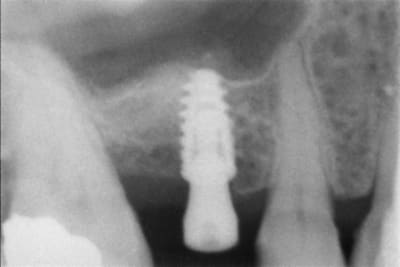

En illustration, j'ajoute des clichés pour RE expliquer pour ceux qu'on pas pigé que c'est opérateur dépendant.

cliché 3 : enfouissement ok : quand c'est posé comme ça avec la bonne vis qui arrive à la bonne hauteur pour la prothèse définitive, on a JAMAIS de souci de "cratère"

cliché 4 : EII sur une 36, l'os a l'air de quand même bien aimer ce col quand la prothèse est à distance...

Moralité : c'est la prothèse qui dicte l'enfouissement, et pas le niveau osseux dispo. Mais ptêt que certains font autrement, après faut pas chercher pourquoi on cratérise : l'espace biologique.

NB : aussi faut pas le torquer comme un porc, c'est sûr, surtout en os dense...